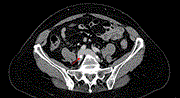

Presentation and management of IVC and iliac vein encroachment by lumbar pedicle screws: a case-report

Keith George and others

Journal of Surgical Case Reports, Volume 2020, Issue 3, March 2020, rjaa040, https://doi.org/10.1093/jscr/rjaa040